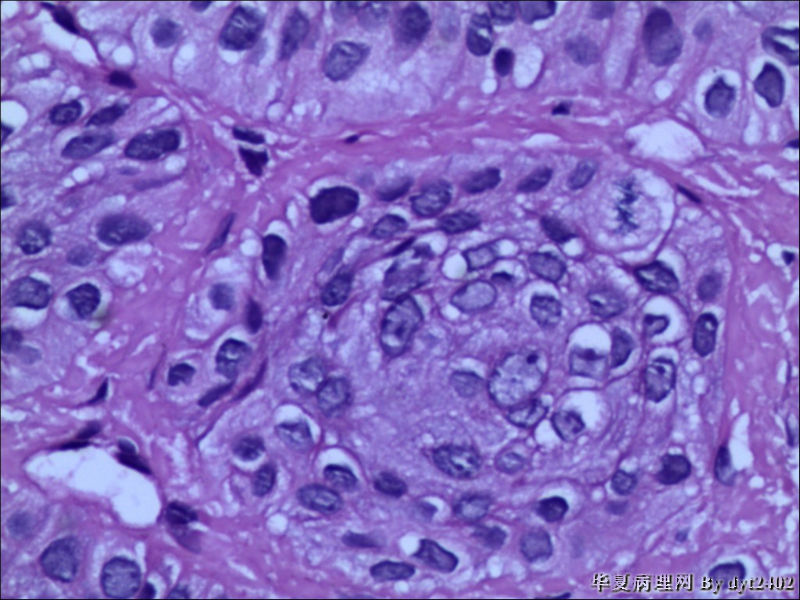

这样的外阴病变 发个原位癌是否合适?

图1